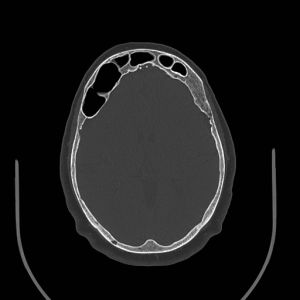

Orbital and brain imaging with magnetic resonance imaging (MRI) with and without contrast should be considered in patients with PSD.[6] In addition, a computed tomography (CT) scan may be helpful for the bony and sinus anatomy. This is essential not only to characterize the sinuses but also to look closely for possible associated arachnoid cysts or meningiomas. The expected finding in PSD is a dilated, air-filled sinus extending beyond the normal boundaries of its bone.[5]